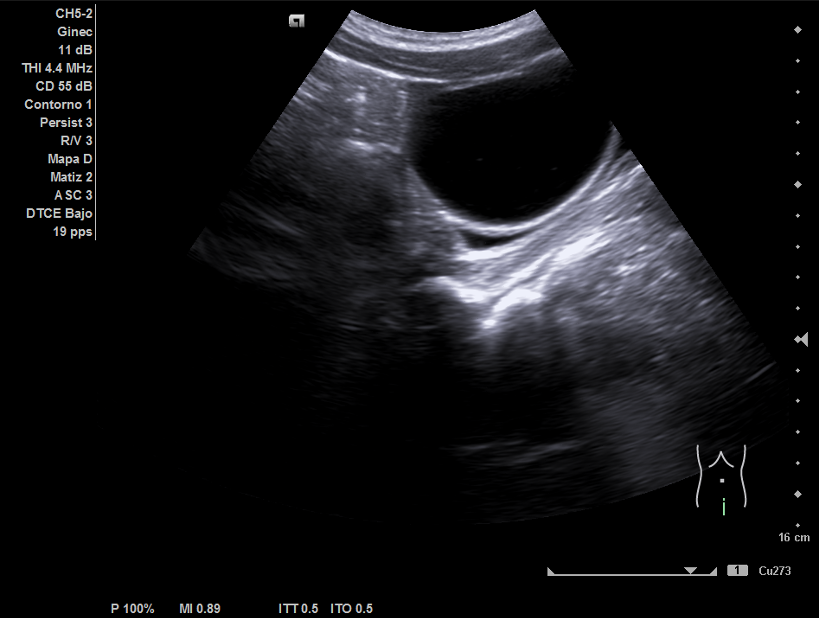

Ecografía abdominal: hígado y vesícula sin alteraciones. Riñones de ecoestructura normales. Útero de características normales. Se apreció imagen anecoica de 7x7 cm que parecía depender de ovario derecho.

En Ginecología se realizó ecografía ginecológica transrectal en la que se confirmó quiste ovárico derecho de unos 79 mm de contenido líquido sin tabiques ni papilas. Con el diagnóstico de crisis de pseudotorsión ovárica se programó para cistectomía de ovario derecho. La anatomía patológica confirmó la presencia de un cistoadenoma mucinoso.